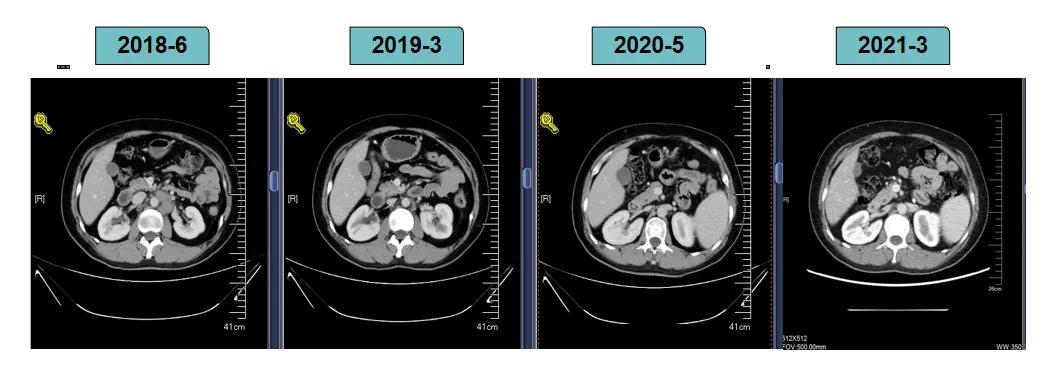

胸腹部增强CT示(2018-6-28):胸骨后占位,肝内异常强化灶,腹膜后肿大淋巴结。

靶病灶:腹主动脉左侧和下腔静脉右侧淋巴结

非靶病灶:肝左叶、肝右前叶下段;纵膈胸骨后淋巴结节;前上纵膈淋巴结;腹膜后小淋巴结

影像学评估-肝脏:

影像学评估-腹膜后淋巴结: